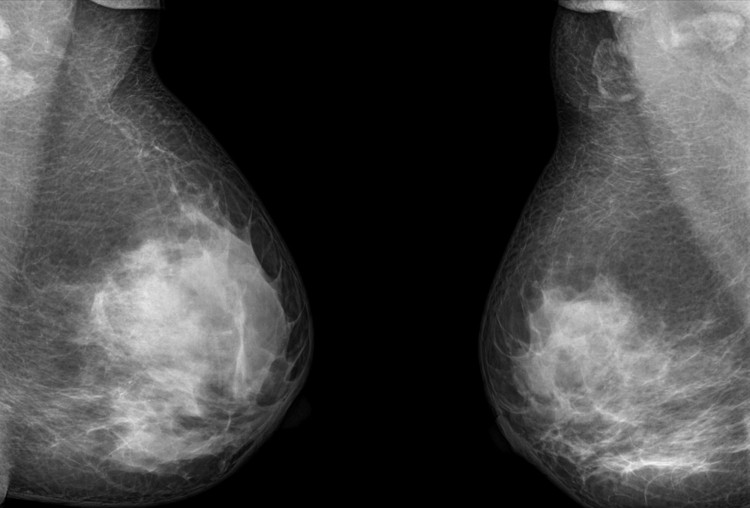

Cách phát hiện sớm ung thư cổ tử cung

Bệnh ung thư - 09/03/2020

Phụ nữ tuổi từ 21 đến 29 nên làm xét nghiệm Pap 3 năm một lần, từ 30 đến 64 tuổi thực hiện thêm xét nghiệm HPV.